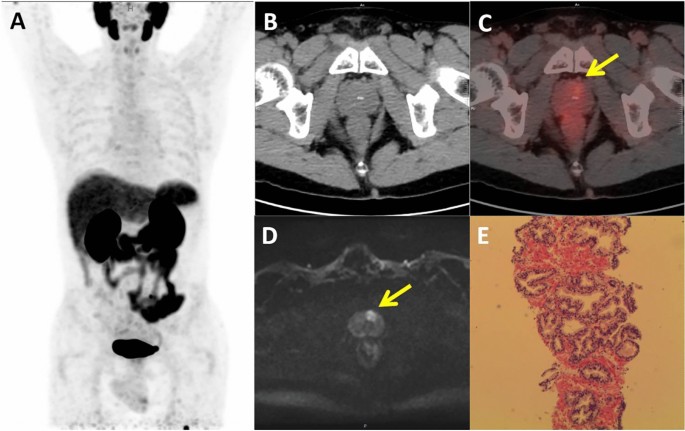

In semi-quantitative analysis, the SUVmax value for the prostate cancer group was 13.1 ± 8.6, significantly higher than the 3.4 ± 1.4 in the benign lesion group (P < 0.05). The optimal diagnostic threshold for SUVmax, determined by the Youden index, was 4.17. Using this threshold, [18F]DCFPyL PET/CT imaging demonstrated a sensitivity of 92.3%, specificity of 88.2%, positive predictive value of 85.7%, negative predictive value of 93.8%, and accuracy of 90.0%. The typical case is shown in Fig. 1. The AUC from ROC analysis was 0.94. The semi-quantitative analysis of SUVmax values from [18F]DCFPyL PET/CT imaging showed high consistency with histopathological results (K = 0.80, P < 0.05). All prostate cancer lesions with a PI-RADS score of 4 presented significantly increased metabolic activity, with SUVmax ranging from 4.18 to 27.85, and the semi-quantitative analysis of [18F]DCFPyL PET/CT imaging exhibited 100% sensitivity and negative predictive value. One false-negative case had an SUVmax of 3.41 but was later confirmed as prostate cancer with a Gleason score of 3 + 3 and an miPSMA score of 1. Two false-positive cases had SUVmax values of 4.99 and 7.55, but their final pathology confirmed prostate inflammation with miPSMA scores of 1 and 3, respectively.

A 63-year-old male with a TPSA level of 7.44 ng/ml. [18F]DCFPyL PET/CT (A, B, C) No significant abnormal increase in radiation was observed in the prostate gland, miPSMA score of 1, SUVmax of 3.6. mpMRI Diffusion-Weighted Imaging (DWI) (D) The transitional zone at the base of the left prostate shows significant high signal intensity, PI-RADS score of 4. Histopathology (E) Nodular hyperplasia of the prostate with slight glandular urethritis changes in the urethral mucosa.